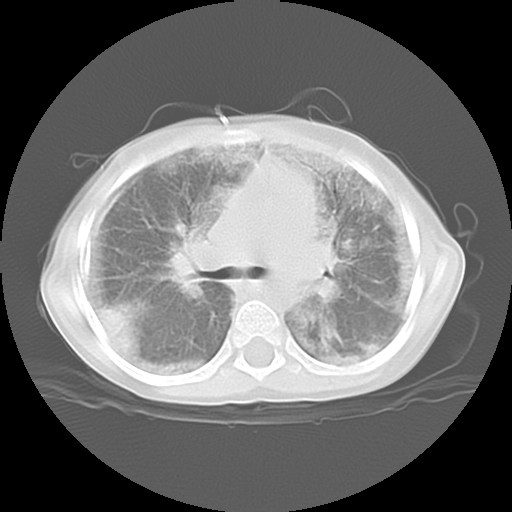

![]() Figure 3 |